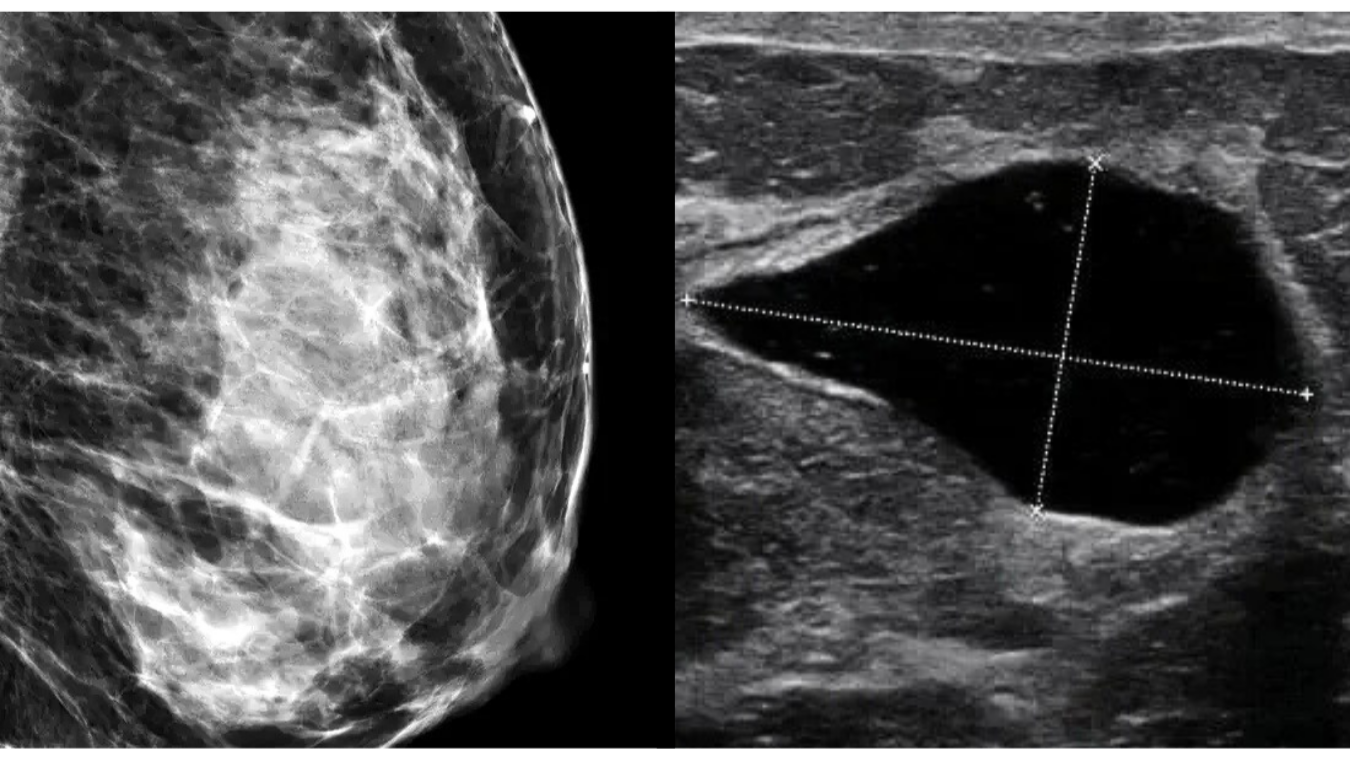

On the left image, the patient’s high breast density prevents the cyst from showing on the mammogram.

On the right, the cyst is clearly visualized on ultrasound as a black area because high density does not obscure the image.